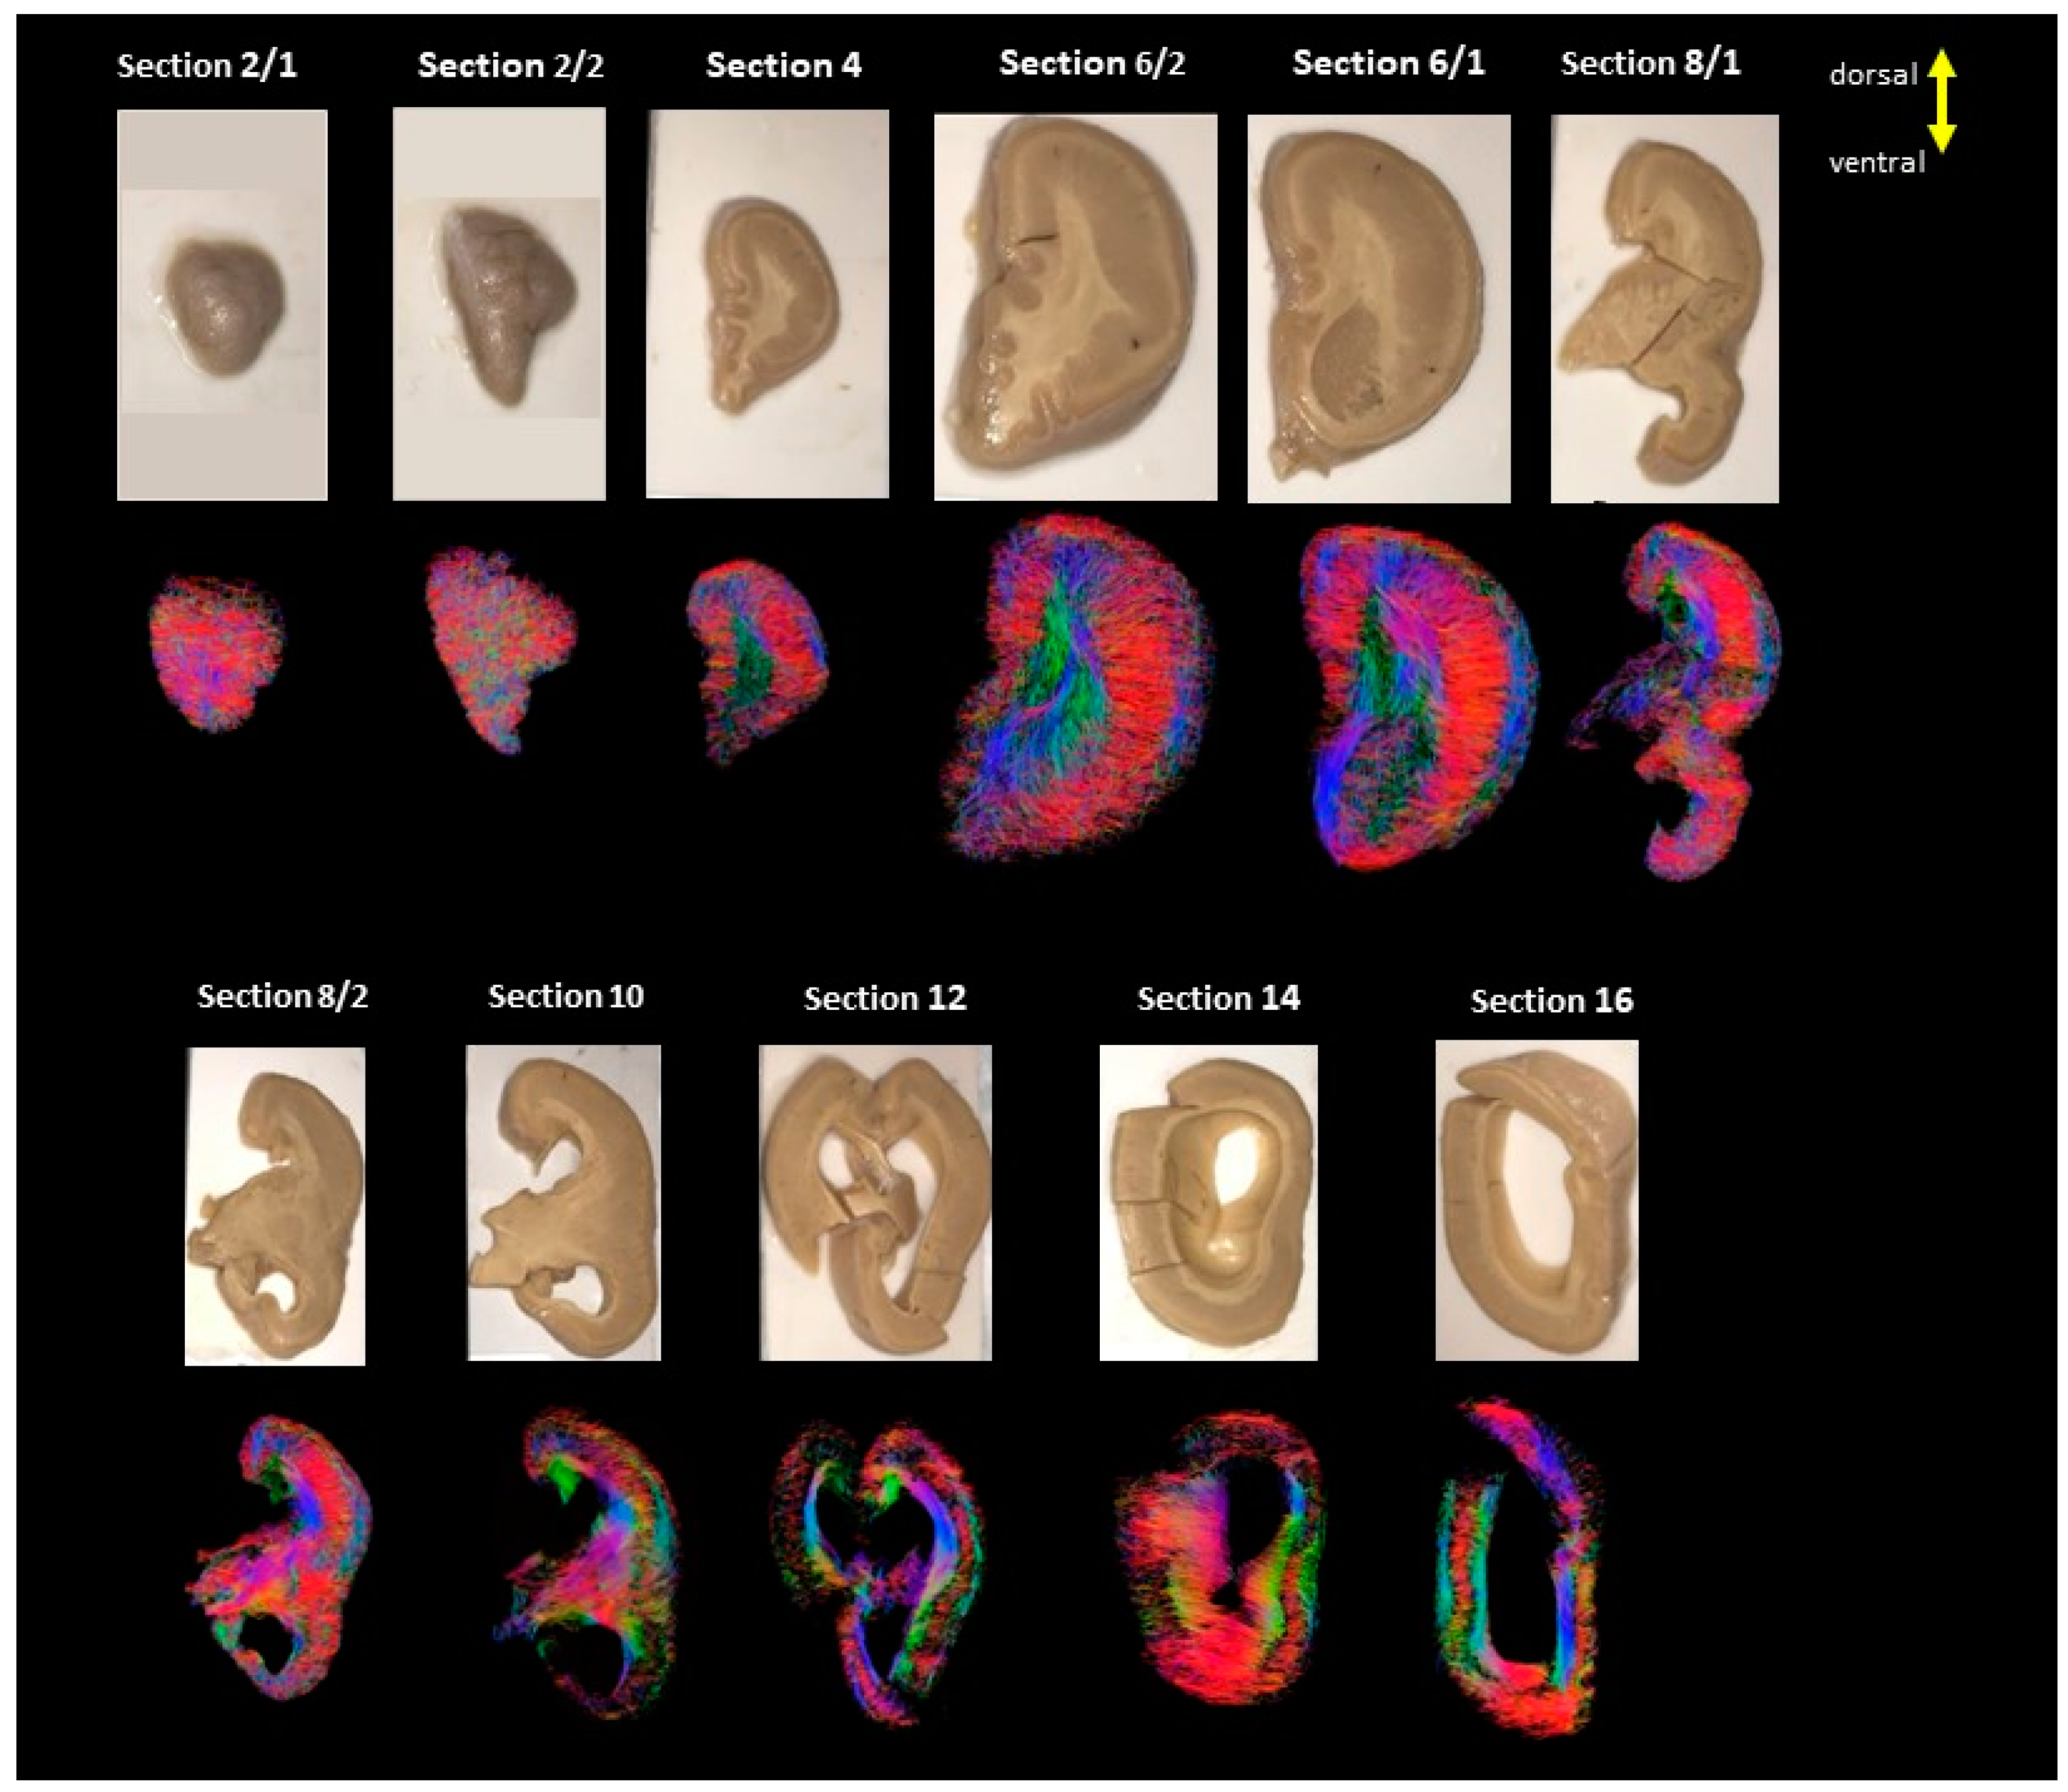

2. Materials and Methods

2.1. Diffusion MRI Acquisition and Analysis

3. Results